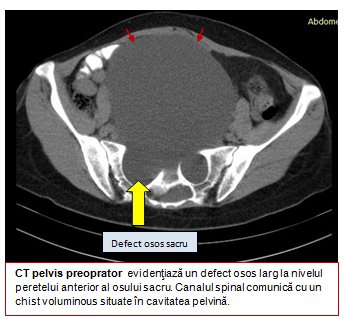

Investigaţii imagistice detaliate, RMN şi CT, au permis evidenţierea unui meningocel sacrat anterior gigant. Acesta reprezintă extensia în cavitatea pelvină a nervilor şi a meningelui spinal, ca urmare a unei anomalii complexe de dezvoltare a porţiunii terminale a coloanei vertebrale, în care câteva dintre vertebre se dezvoltă incomplet. Porţiunea terminală a coloanei vertebrale este fixă, fiind formată din vertebrele sacrate fuzionate, de unde denumirea de os sacru.

În interiorul osului sacru se continuă canalul spinal, care conţine sacul meningeal şi fluidul spinal în care se găsesc nervii sacraţi, care asigură controlul vezicii urinare, al sfincterului anal şi sensibilitatea din regiunea bazinului şi a organelor genitale.